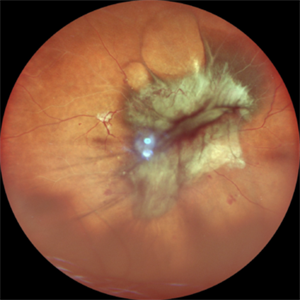

The Macular Forest

Central fundus photograph of a 60 year-old woman with advanced proliferative diabetic retinopathy shows extensive neovascularization at the macula.

Photographer: SHISHIR VERGHESE

Condition/keywords: neovascular frond, neovascular membrane, proliferative diabetic retinopathy (PDR)